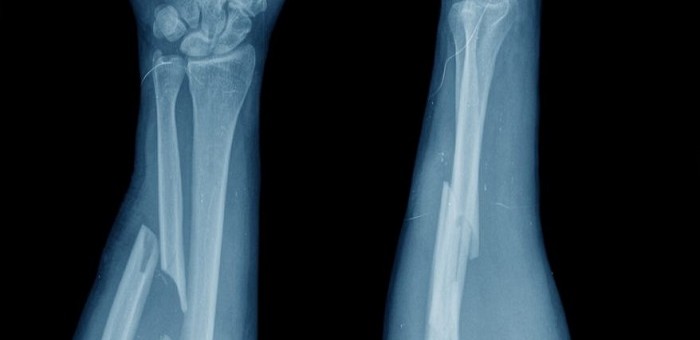

Referat Ocena ryzyka złamań patologicznych z wykorzystaniem technik cyfrowej analizy obrazu wygłosi: dr n. med. Piotr Biega, Katedra Fizyki i Inżynierii Medycznej PRz, Oddział Ortopedii Onkologicznej, Szpital Specjalistyczny w Brzozowie: Podkarpacki Ośrodek Onkologiczny